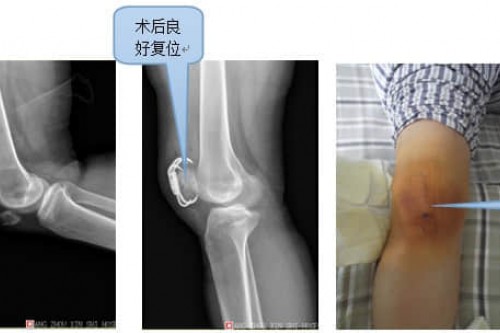

真实案例展示案例三 伤者钟女士,女,34岁,因右髌骨粉碎性骨折入院。入院后立即行开放复位内固定术,切口使用美容缝合。手术骨折复位满意,固定牢靠,术后1周下床活动。 如有疑问请与广东药学院附属第三医院专家联系,咨询预约QQ:4006011205、咨询预约电话